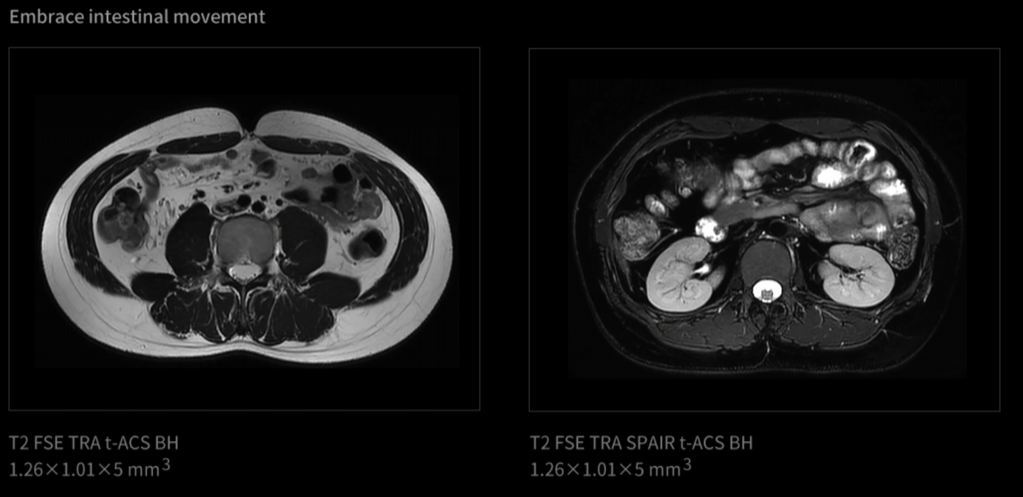

uAIFI.LIVE je nejnovější inovativní platforma, která slouží jako inteligentní řídicí jádro systému, integrující klíčové technologie magnetické rezonance s cílem dosáhnout časoprostorového zobrazení lidského těla. Podobně jako špičková filmová kamera, systém uMR Ultra využívající platformu uAIFI.LIVE zásadně mění paradigmu MR – posouvá zobrazování od tradičního statického snímkování ("fotografie") k dynamickému sekvenčnímu zobrazení ("videografie").

Otevřený tunel o průměru 70 cm, gradient 100 mT/m a 200 T/m/s umožňují ultra-rychlou uzávěrku a plynulé snímání pohybu.

Sledujte život v pohybu

Od vzniku magnetické rezonance je pohyb jednou z největších výzev při zobrazování. Celá desetiletí byly v tomto odvětví zkoumány různé technologie pro „zmrazení pohybu“. Inovace uMR Ultra dnes slibuje svět MRI bez omezení pohybu – oblast, ve které můžeme pozorovat skutečný stav lidského těla. Jelikož otevíráme novou dimenzi zobrazování pomocí MR, je komplexní transformace diagnostických standardů nevyhnutelná.